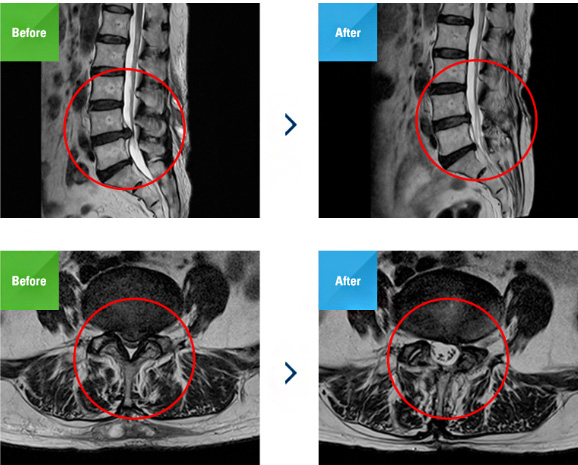

최소침습 미세현미경 감압술은 기존의 척추관 협착증 수술방법인 미세현미경 감압술을 보완한 수술법이며, 최소침습으로 시행하여 절개부위가 작고 수술시간이 단축되며 출혈도 훨씬 적습니다. 아주 미세한 절개(1.5cm) 후 튜브를 삽입하여 수술 부위에 정확히 위치시킨 뒤 미세현미경을 통해 내부를 보면서 척추관 내의 신경을 압박하는 병변을 제거합니다. 한쪽의 작은 절개로도 반대편의 척추관까지 접근하여 치료 가능합니다.

미세한 절개(1.5cm) 후 튜브를 삽입하여 수술 부위에

정확히 위치시킨 뒤

미세현미경을 통해 내부를 보면서

척추관 내의 신경을 압박하는 병변을 제거합니다.